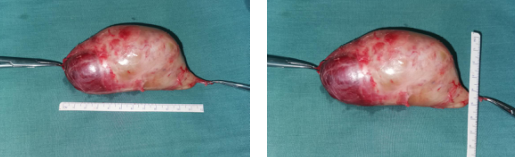

次日,手术按时进行,术中探查见肿物与臂丛神经相连,上肢的一些主要的动、静脉都在肿物的下方。手术风险性非常大,稍有不慎,就会损伤血管造成大出血的状况,且难以修补。术中按照术前拟定的手术方案,采取锁骨上、下切口,通过锁骨下隧道方式仔细剥离肿物上神经束,术中见神经瘤与神经粘连严重,予以松解,于锁骨上下切口内采取“会师法”将神经瘤完全剥离。经过4个小时的努力,手术顺利完成。取出的肿物经过测量,大小约12cm×6cm×5cm,竟然比一个拳头还要大。

肿物取出后用术中肌电图生理检测臂丛神经呈现正常电生理表现,手术过程中很好地保护了臂丛神经。

术后肿物送病理检查再次明确诊断为神经鞘瘤。